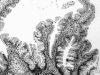

Figure 1

Histological findings of a serrated adenoma in case No 10. The lesion is composed of epithelial cells of prominent nuclei in serrated grandular structures. These findings are compatible with a serrated adenoma.